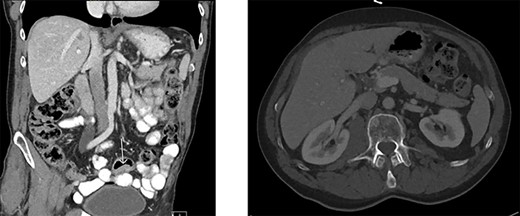

Colonoscopy revealed a polyp in the sigmoid colon and an obstructing tumor suspected for CRC (20 cm from the anal verge) (Fig. 1). An abdominal contrast-enhanced computed tomography showed four lesions in the liver suspected for metastases without lymphadenopathy (Fig. 2). Magnetic resonance of the liver showed five lesions suspected for metastases. Chest X-ray was normal.

Colonoscopy of the sigmoid colon revealing a polyp suspected for malignancy.